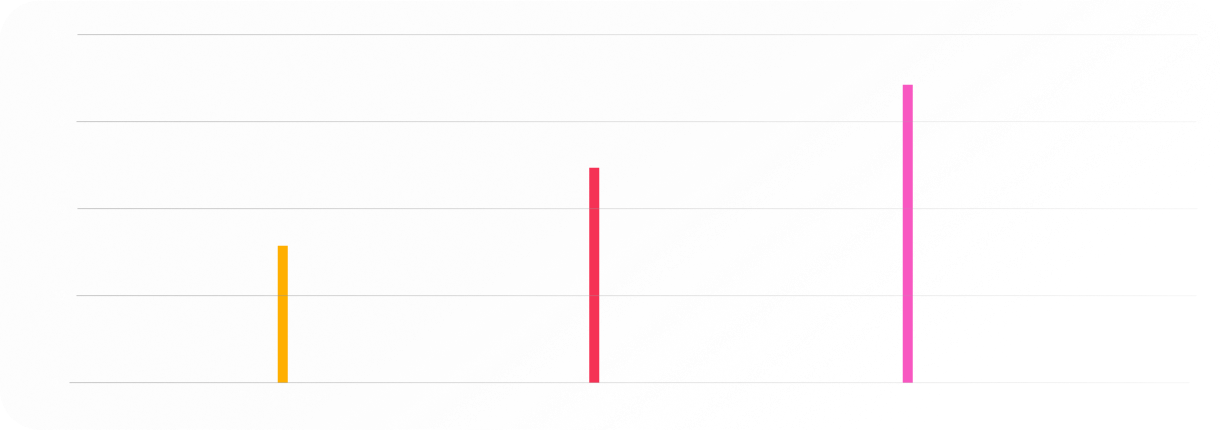

Low T Comorbidities

36.5% of men with

type 2 diabetes have low T4

50% of men who

are overweight have low T5

67% of men suffering

from erectile dysfunction

have low T6

Men with Low T are 4x more likely to be diagnosed with clinical depression7

Low T can be a cause of osteoporosis in older men8